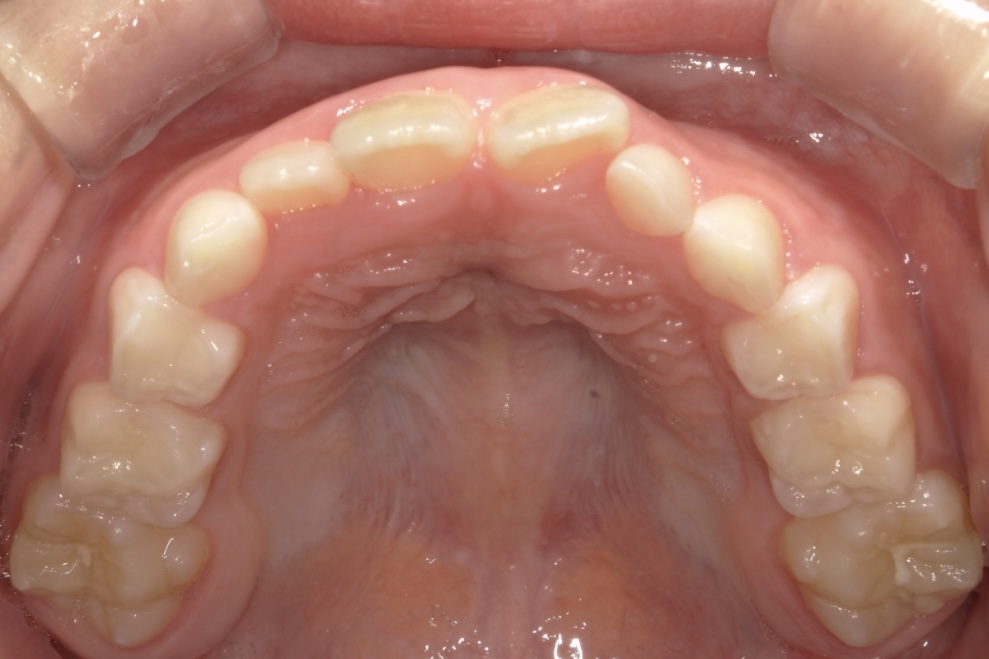

BEFORE

9歳男児 すきっ歯とガタガタが気になる

主訴は歯並びのガタつきとすきっ歯でした。できるだけ痛みや不快感の少ない方法で治療を進めたいとのご希望をお持ちでした。